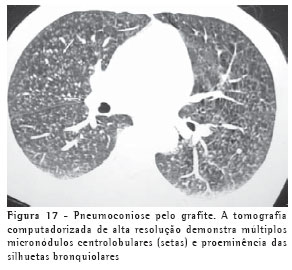

Além da sílica e do asbesto, outros agentes podem ser causadores de doenças respiratórias ambientais e ocupacionais. Na pneumoconiose pelo grafite, os achados tomográficos mais comuns são micronódulos pulmonares, espessamentos septais e opacidades parenquimatosas (Figura 17).(23)